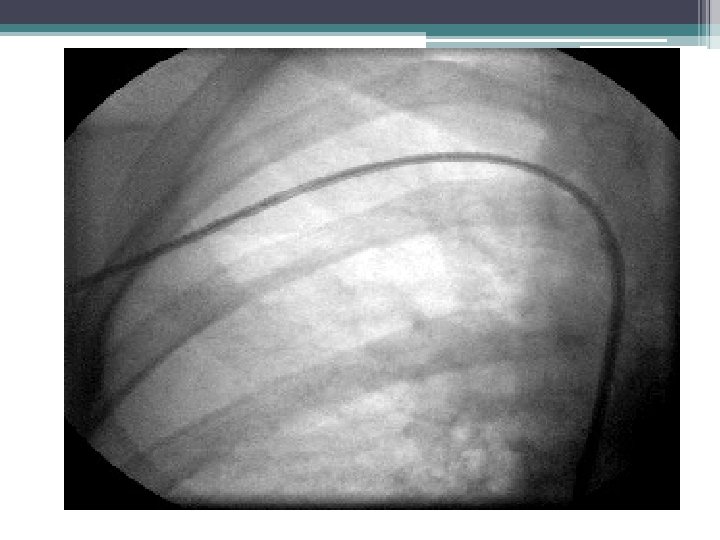

Common Areas of Fibrosis